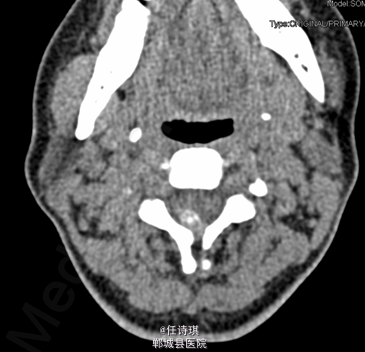

女,46岁8月,因“颈部不适3年,右上肢软弱疼痛伴双下肢胀痛1年”入院。3年前无明显诱因出现颈部不适,以局部胀痛为主,劳累后加重休息后可缓解,不伴上肢放射痛。遂未予特殊处理。1年前出现右上肢酸麻肿痛,以肘关节疼痛和手部皮肤麻木为主,行走约10分钟后自觉双小腿后侧胀痛,休息后可缓解。在当地医院诊断为“网球肘、颈椎病”予以对症治疗,但上述症状无明显改善。行MRI、CT等检查,诊断为“C2椎管内肿瘤”,未予特殊治疗。为求进一步诊断今日由门诊以“C2椎管内占位,性质?”收入院

专科查体:视:脊柱无明显畸形。触:颈胸部各棘突无明显压、叩痛。四肢肌张力正常,右手皮肤触觉减退。动量:右侧上肢肌力IV级,左侧肢体V级。右侧上肢腱反射活跃,双侧膝腱反射活跃,跟腱反射正常引出。Hoffman征阳性,Babinski征未引出。外院MRI示:C2椎管内脊髓背侧占位病变,脊膜瘤可能。T2椎体内异常信号,多为血管瘤。。

初步诊断:1、颈2节段椎管内占位伴不全四肢瘫(Frankel D):脊膜瘤?黄韧带骨化? 2、胸2椎血管瘤 处理:全麻下行经后路颈2全椎板切除、椎管探查减压、椎管内占位切除活检术,